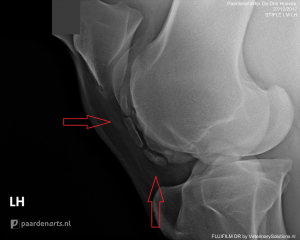

Wanneer de ernst van het letsel niet met zekerheid vastgesteld kan worden aan de hand van regulier onderzoek, kan er een röntgenfoto gemaakt worden. Bijvoorbeeld bij verdenking van een botbreuk (zie foto).

Bij kreupelheidsdiagnostiek wordt het paard nauwkeurig onderzocht. Röntgenonderzoek kan helpen om bepaalde aandoeningen of oorzaken aan het licht te brengen. Bij kreupelheidsdiagnostiek kan bijvoorbeeld middels röntgenbeelden gewrichtsartrose zichtbaar worden evenals een ontsteking aan het botvlies, hoefkatrolontsteking, fracturen, scheurtjes etc.